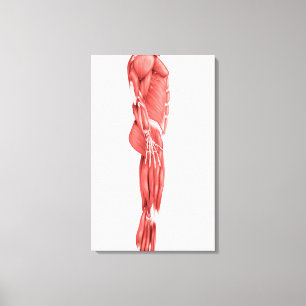

Lienzo Ilustracion médico del sistema muscular masculino

Precio 187,00 €